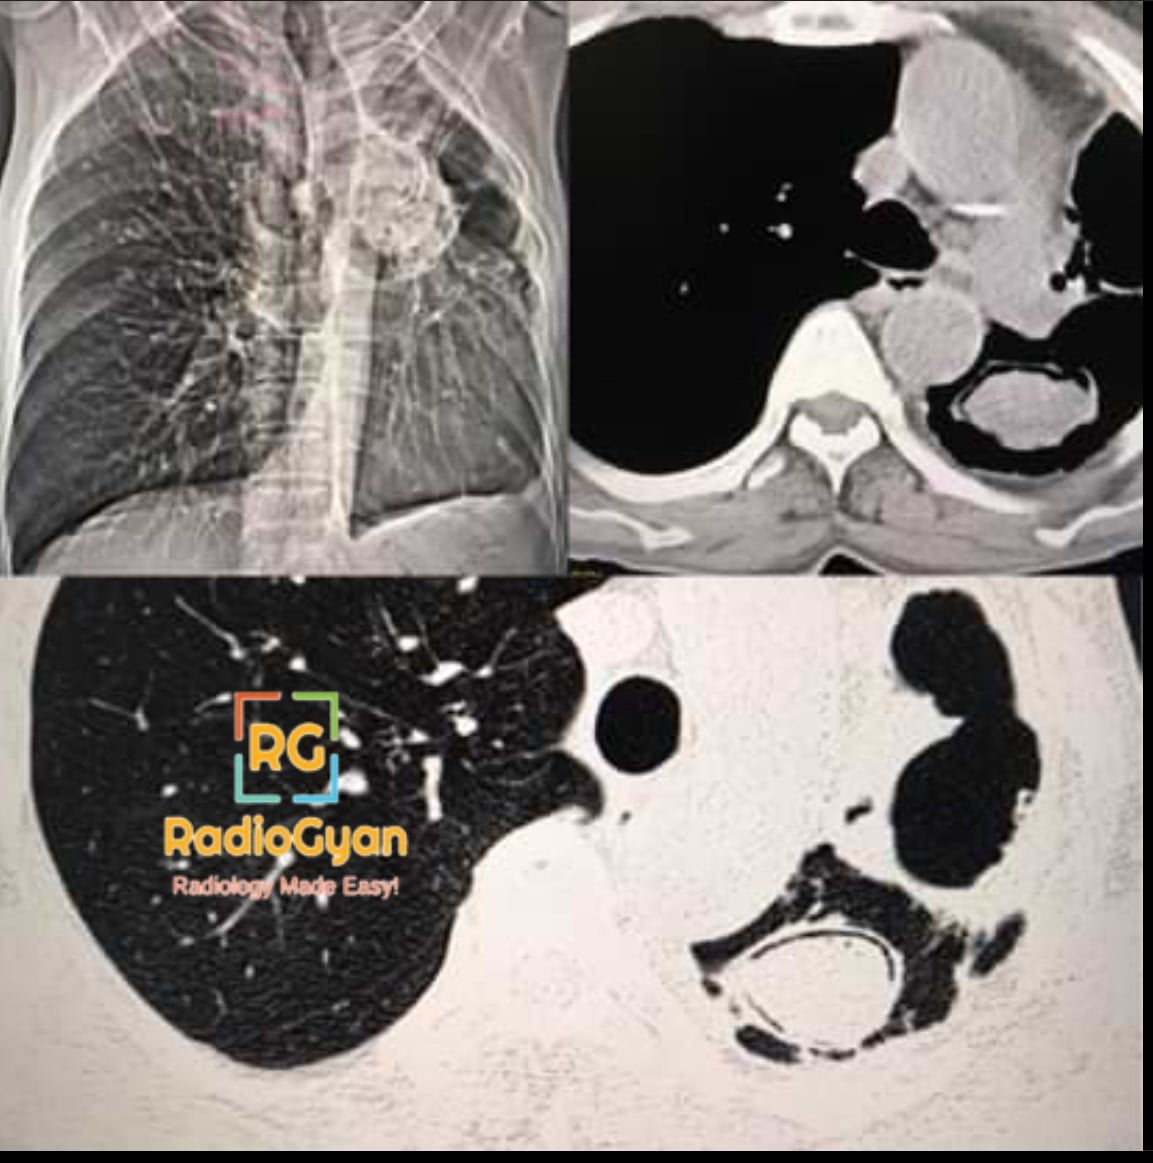

The air crescent sign results from the formation of a crescent-shaped collection of air between a central intracavitary mass or necrotic tissue and the surrounding lung cavity wall. It is most commonly seen in fungal infections such as aspergilloma (a fungal ball caused by Aspergillus species) growing within pre-existing lung cavities. It can also occur due to necrotic pulmonary lesions where necrotic lung tissue detaches from the cavity wall, such as in recovering invasive pulmonary aspergillosis. The sign signifies partial separation of the mass or necrotic material from the cavity, often associated with underlying cavitary pulmonary diseases including tuberculosis, sarcoidosis, or neoplasms.

The sign develops when air collects between the cavity wall and an adjacent mass or necrotic tissue that has begun to separate or retract. This separation occurs as the central lesion loses adherence from the cavity wall due to necrosis or fungal colonization, allowing air to fill the space and produce a characteristic crescentic radiolucency on imaging. The crescent shape reflects partial circumferential separation rather than complete detachment of the intracavitary lesion.